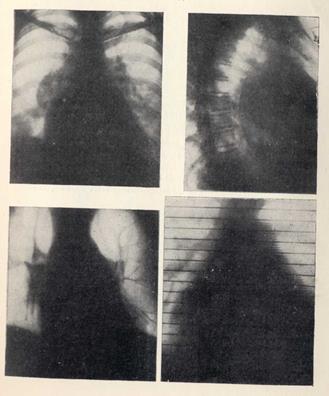

РЕНТГЕНОГРАММЫ БОЛЬНОГО С ВЫРАЖЕННОЙ НЕДОСТАТОЧНОСТЬЮ ДВУСТВОРЧАТОГО КЛАПАНА.

В прямой проекции типичная митральная конфигурация: увеличение сердца в обе стороны; фаза легочной гипертензии: корни расширены, особенно справа, в виде крупного узла. В первой косой проекции — оттеснение контрастированного пищевода по дуге большого радиуса. На томограмме видно аневризма-тическое расширение устья впадения правой верхней легочной вены, переходящее в расширенное левое предсердие (бесконтрастная кардиография). На рентгенокимограмме выявляется признак вентрикуляризации зубцов ушка левого предсердия.